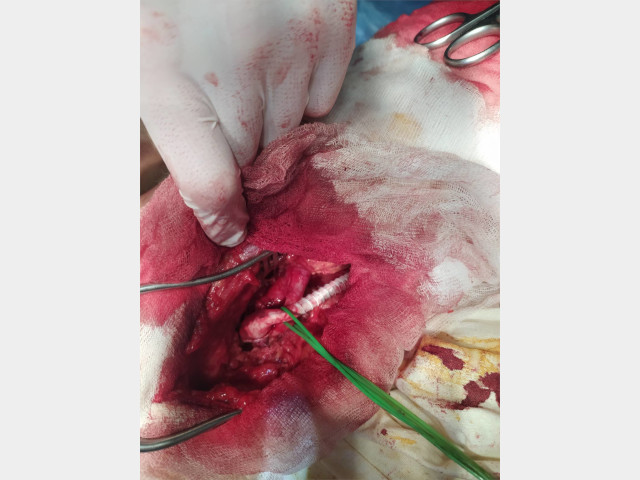

Хирургическая помощь

В ГУ «ЛРКБ» ЛНР ОСХ сотрудниками кафедры госпитальной хирургии и онкологии и врачами ГУ «ЛРКБ» ЛНР ежедневно оказывается специализированная хирургическая помощь больным с атеросклерозом магистральных артерий нижних конечностей.

Пациент 1.

Диагноз: Мультифокальный атеросклероз. Стеноз внутренней сонной артерии 20% справа и 25% слева. ХНМК 1. Стеноз общей подвздошной артерии 75% справа и 65% слева. Окклюзия бедренно-подколенных сегментов с обеих сторон. ХИНК II Б степени справа и ІІ А степени слева.

26.02.2020 производилось плановое оперативное лечение пациенту с многососудистым атеросклеротическим поражением.

Больному было сделано аорто–бифеморальное шунтирование и протезно–подколенное шунтирование справа. (Операционная бригада: Лящук А.В., Нижельский В.Е., Редин Д.Е.; Анестезиолог: Никитич А.В.)

После операции у больного пульс на оперированной стопе нижней конечности.

Пациент 2.

Диагноз: Мультифокальный атеросклероз. Стеноз 20% внутренней сонной артерии с обеих сторон. ХНМК 1. Окклюзия бедренно-подколенного сегмента слева. ХИНК II Б степени слева. (Операционная бригада: Лящук А.В., Нижельский В.Е.; Анестезиолог: Долженко С.В.).

03.03.2020 - производилась плановое оперативное лечение пациенту с окклюзией левой поверхностной бедренной артерии.

После операции у больного пульс на оперированной стопе нижней конечности.

Ассистент кафедры госпитальной хирургии и онкологии А.В.Лящук